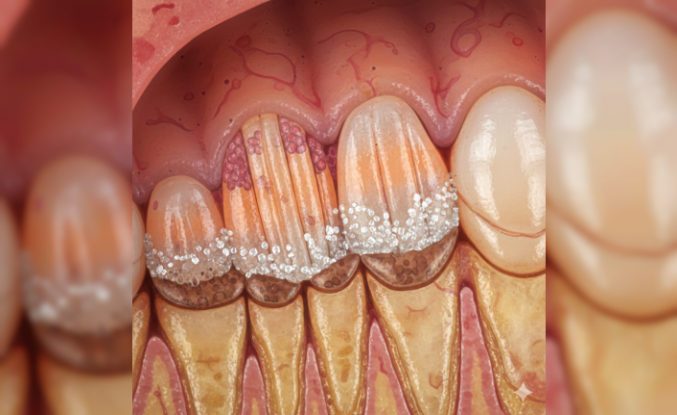

Ciltteki Koyu Lekeler Hastalık Habercisi Olabilir mi?

Vücudun belirli bölgelerinde aniden ortaya çıkan kadifemsi koyu renkli değişimler, sanılanın aksine sadece bir hijyen sorunu değil. Uzmanlar boyun, koltuk altı ve kasık bölgelerinde görülen acanthosis nigrcans (deri kalınlaşması) durumuna karşı vatandaşları uyarıyor. Ciltteki değişimler bazen kritiktir. Çoğu kişi bu lekeleri güneş yanığı veya kir sanarak keselemeye çalışsa da mesele aslında derinin altında yatan metabolik süreçlerle ilgili.